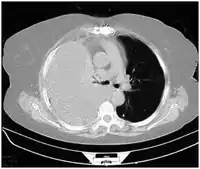

Computed tomography (CT or CAT) scans may be useful for diagnosing retained hemothorax as this form of imaging can detect much smaller amounts of fluid than a plain chest X-ray. However, CT is less used as a primary means of diagnosis within the trauma setting, as these scans require a critically ill person to be transported to a scanner, are slower, and require the subject to remain supine.[23][26]

CT scan of the chest showing a hemothorax caused by warfarin use